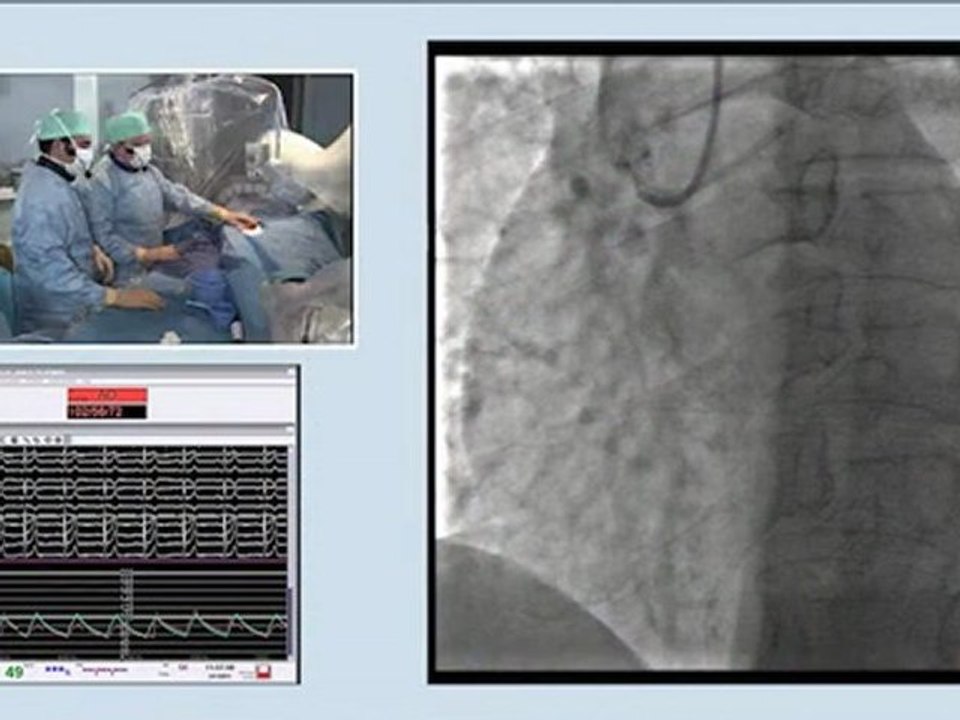

10 tibio-peroneal artery atherectomy (rotablator) antegrade approach incathlab.com